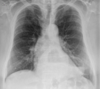

RN a termo.

Cardiomegalia massiva em um neonato com pulmão normal (sem edema alveolar ou intersticial, sem derrame pleural)

Cardiomiopatia neonatal.